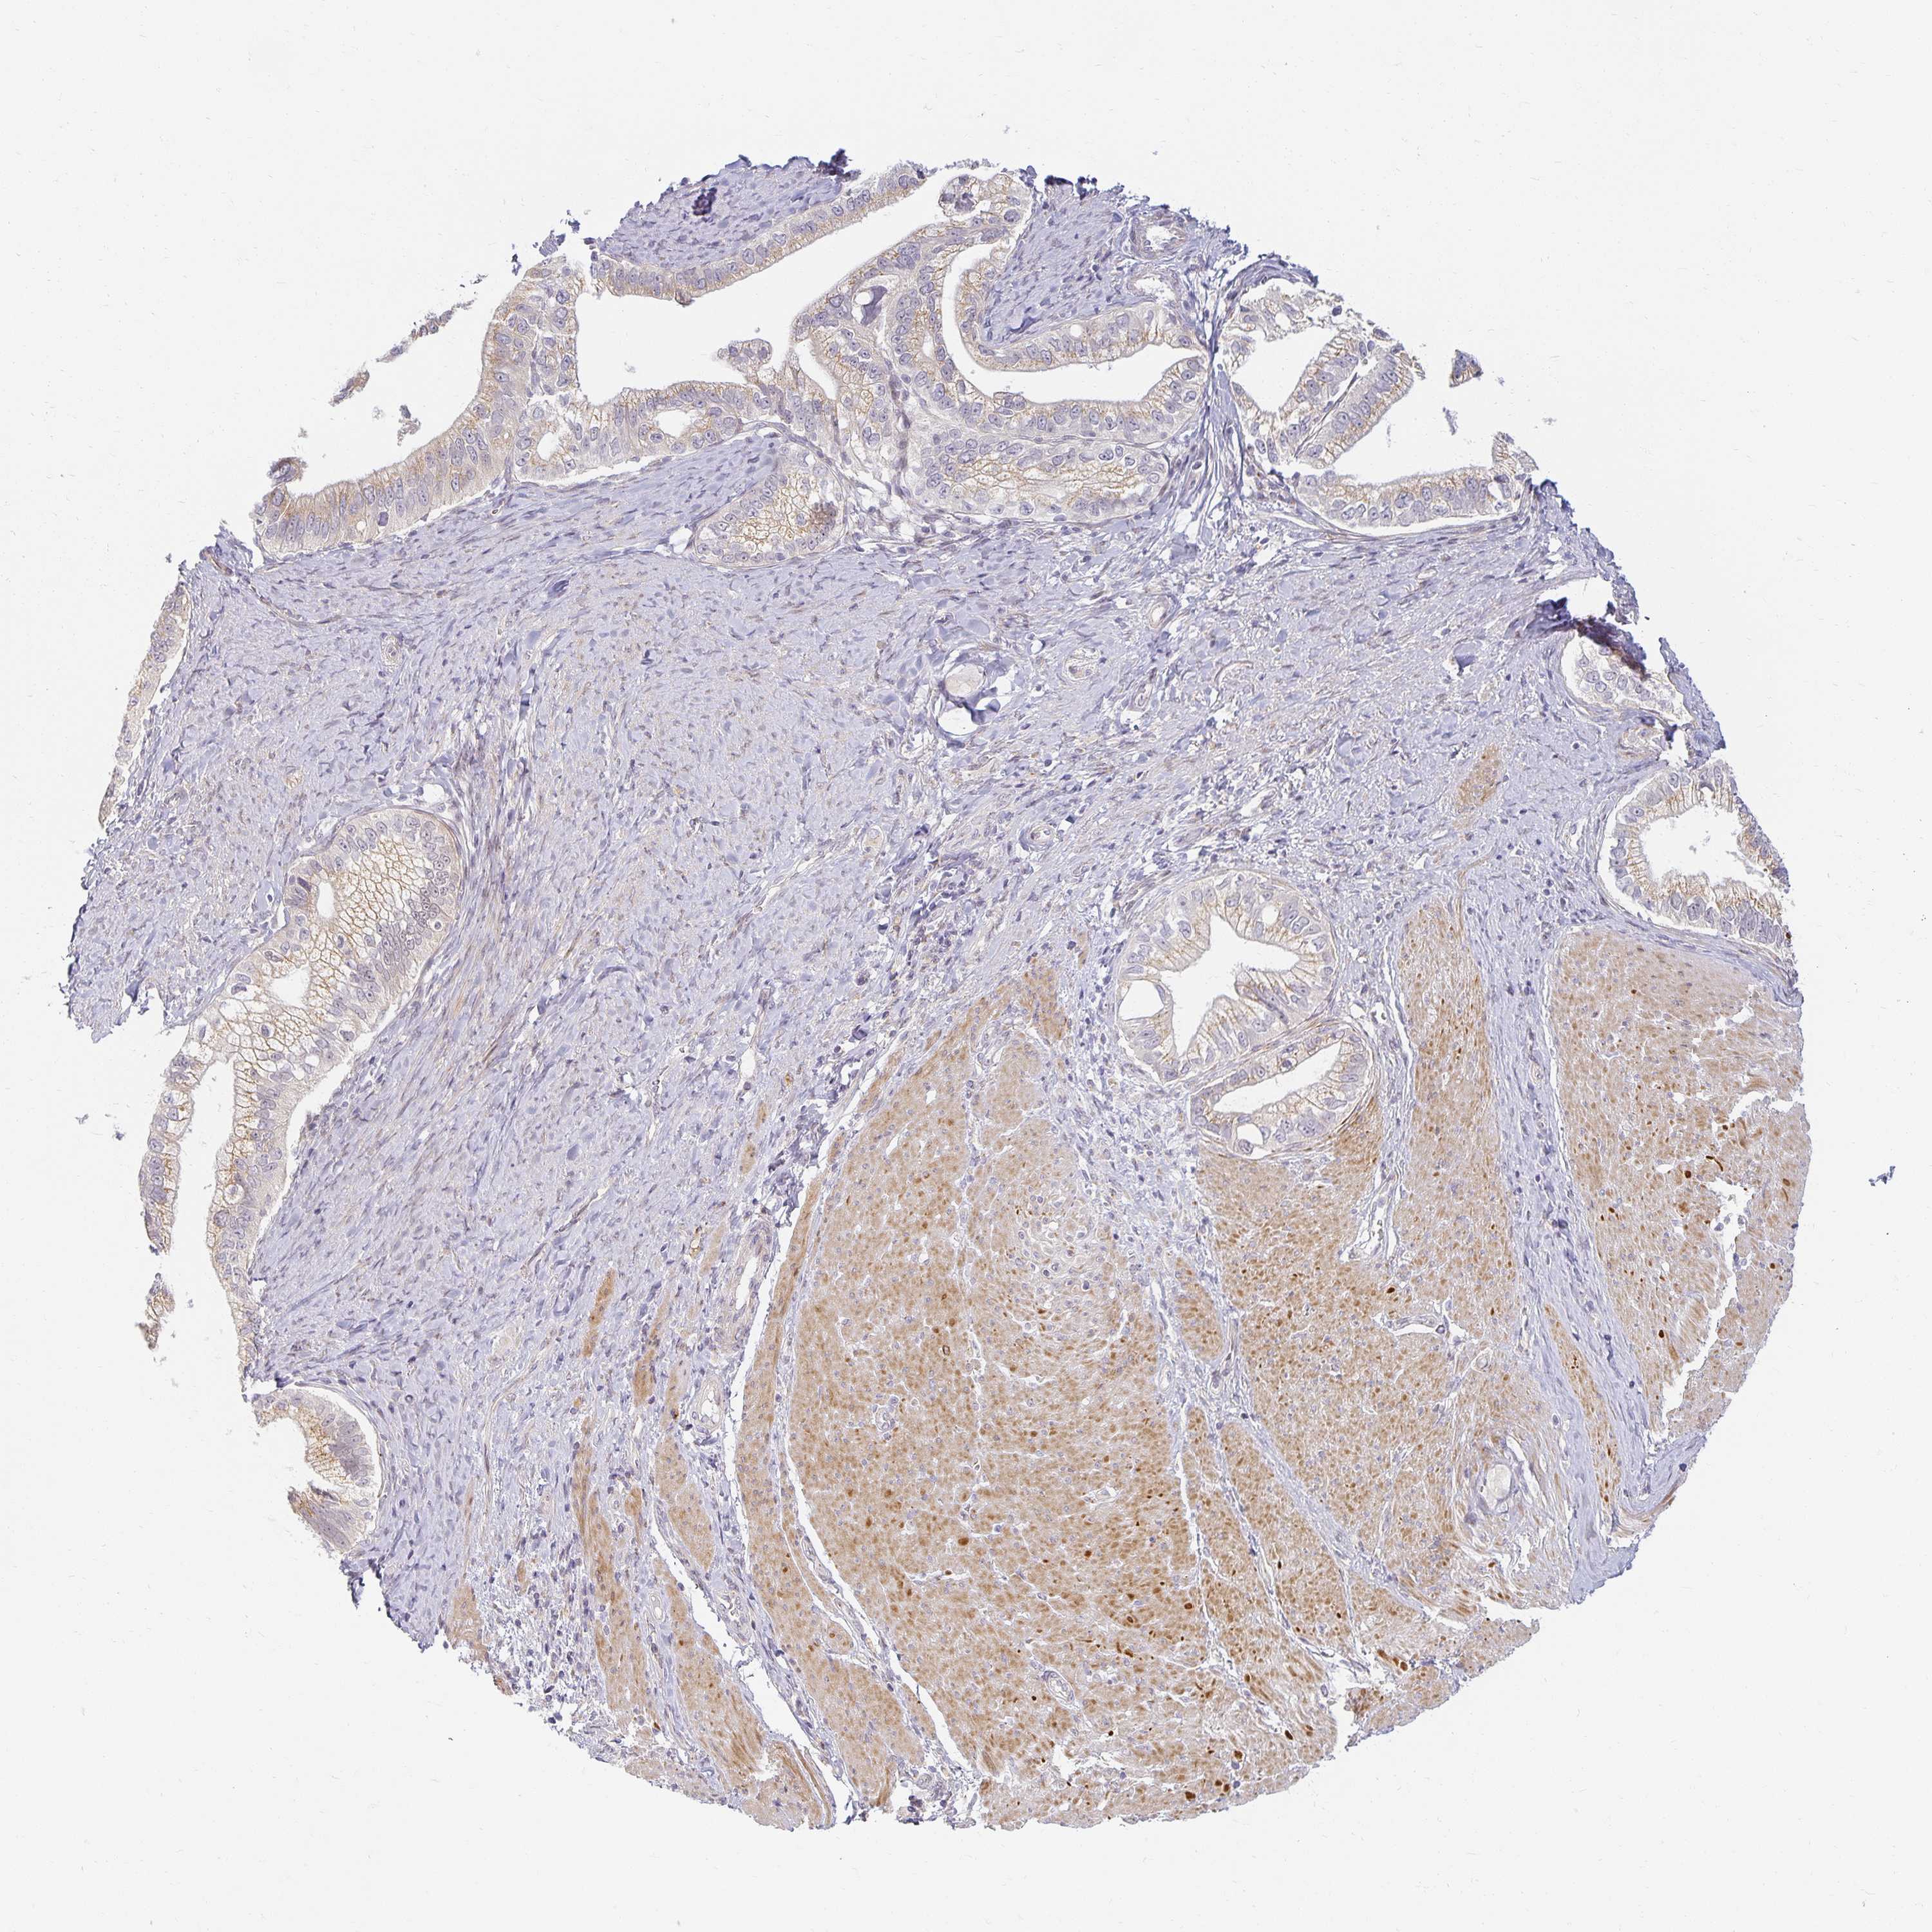

PANCREATIC CANCER - Protein expressioni

A mouse-over function shows sample information and annotation data. Click on an image to view it in a full screen mode. Samples can be filtered based on level of antibody staining by selecting one or several of the following categories: high, medium, low and not detected. The assay and annotation is described here.

Note that samples used for immunohistochemistry by the Human Protein Atlas do not correspond to samples in the TCGA dataset.

Antibody stainingi

Antibody staining in the annotated cell types in the current human tissue is reported as not detected, low, medium, or high, based on conventional immunohistochemistry profiling in selected tissues. This score is based on the combination of the staining intensity and fraction of stained cells.

Each image is clickable and will lead to virtual microscopy that enables deeper exploration of all samples and also displays staining intensity scores, fraction scores and subcellular localization as well as patient and tissue information for each sample.

Antibody HPA060734

Staining

High

Medium

Low

Not detected

Intensity

Strong

Moderate

Weak

Negative

Quantity

>75%

75%-25%

<25%

None

Location

Nuclear

Cytoplasmic/membranous

Cytoplasmic/membranous,nuclear

Adenocarcinoma, NOS